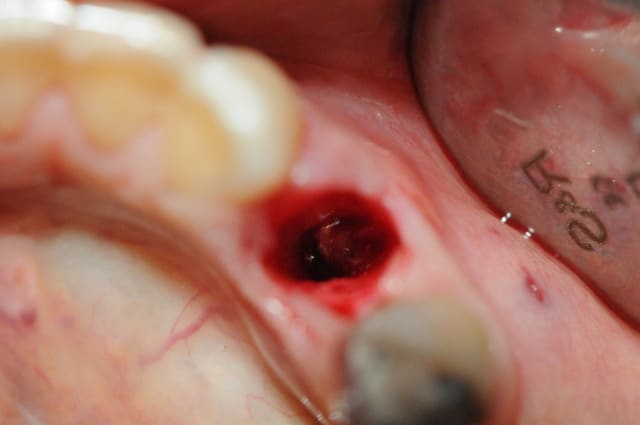

Je viens de faire l'extraction ce matin.

Je rage de ne pas l'avoir fait encore plus tôt car c'est bien ce que je craignais, toute la table externe a été bouffée par l'infection...

J'ai cureté très soigneusement et irrigué puis mis matériaux de comblement pour limiter l'effondrement en vestibulaire.